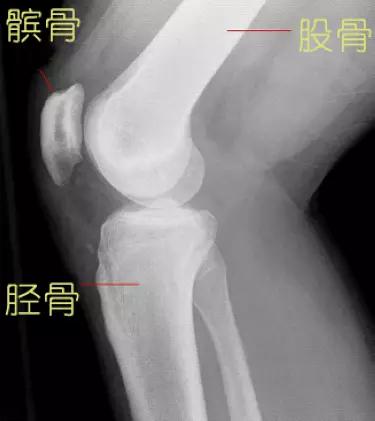

膝关节作为人体最大最复杂的关节,由股骨下端、胫骨上端和髌骨共同构成。其中胫骨上端基本上是一个平面,而股骨下端的关节面则是一个椭圆形,两个关节面一圆一平,并不完全贴和,所以需要半月板来帮助关节面完整贴和。

膝关节X光片(矢状面)